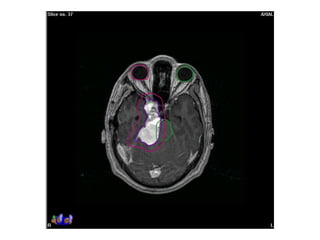

Response to treatment assessment

• ‘Lack of progression’ after conventional RT is considered response

• Increase in size as per RECIST criteria in considered progression

• High dose per fraction induce early regression in meningioma

• SRS (CyberKnife) induce early response with volume reduction

Pre-RT Post-RT: 6 mo

- No significant change in size of mass: stable disease

Response to treatmentassessment • ‘Lack of progression’ after conventional RT is considered response • Increase in size as per RECIST criteria in considered progression • High dose per fraction induce early regression in meningioma • SRS (CyberKnife) induce early response with volume reduction Pre-RT Post-RT: 6 mo - No significant change in size of mass: stable disease